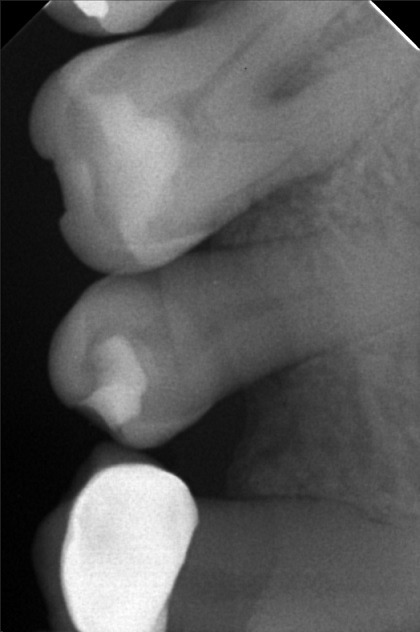

- 6/1/22- perio Tx / deep scaling laser curettage/ laser hypersensitivity/ next meeting FIRST WK august ***for change crown 9/10/22- stain removal 9/17/22 - check up for change crown

- rosario_04.jpg